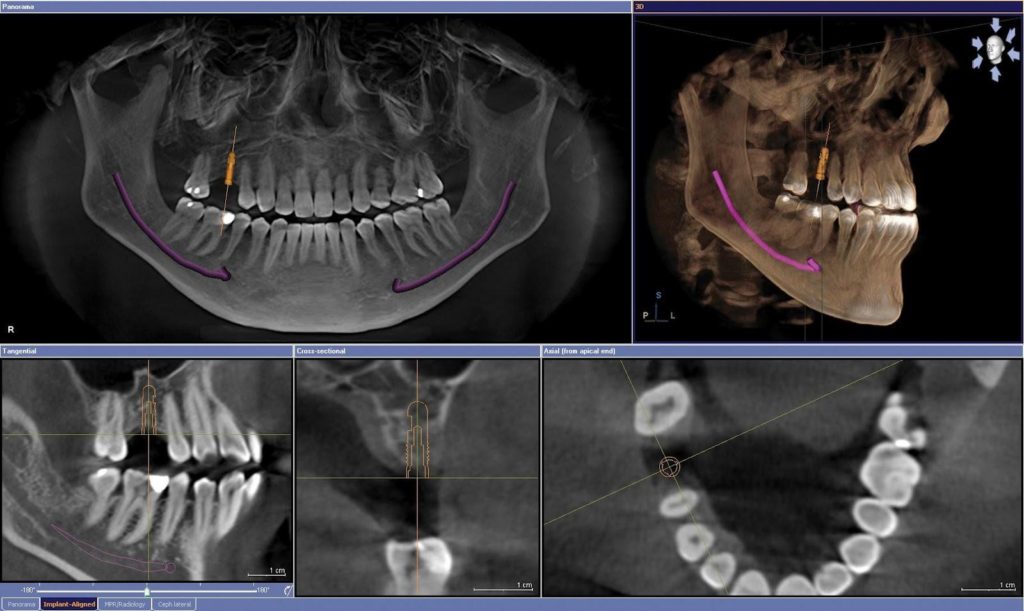

En la primera consulta en la clínica dental el paciente es examinado por un dentista especializado en implantes para conocer el estado de boca, dientes, tejidos y hueso.

El odontólogo lleva acabo distintas pruebas diagnósticas como unas fotos, modelos de estudio y pruebas radiográficas, Tomografía donde nos muestra imagen tridimensional (3D) del espacio donde irán situados los implantes, así como la calidad del hueso donde se van a situar. Todo esto nos dará la informaión para saber que necesidades de material y proceder tendremos para la cirugía.